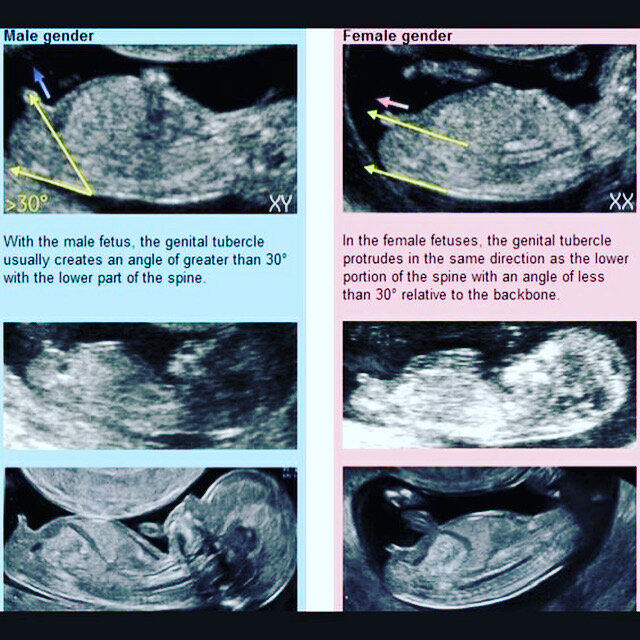

Tak maličké babo zatial neurčí ani lekár, ktorý si vie naštelovať obraz priamo na genitálie. Podľa ,,siluety" plodu ti to nik nepovie a ani nie takto skoro. A aj keby sme tam už my mohli niečo vidieť, foto je tak rozmazaná, že nemáme šancu. V ktorom si tt ?

@gretka575 takto skoro ti pohlavie nepovie ani skúsený lekár. Ono ešte nie je jasne vidno rozdiel, chlapci aj dievčatá vyzerajú v tomto čase rovnako. Napr mne nepovedal ani skúsený lekár grochal v 14 tt a to tou sondou mohol skúšať zo všetkých strán. Poznám ženu, ktorej nevedel lekár povedať ani v 20 tt.

@anonym_ef6eed mne zistil pri poslednom babatku moj lekar v 14tt., bolo to 13+4 konkretne, ze na 80% dievca. A neskor to len potvrdil. Ale v 11? Teraz som bola v 12+6 a povedal mi, ze sa pozeral, ale nevie povedat, ze je este skoro.